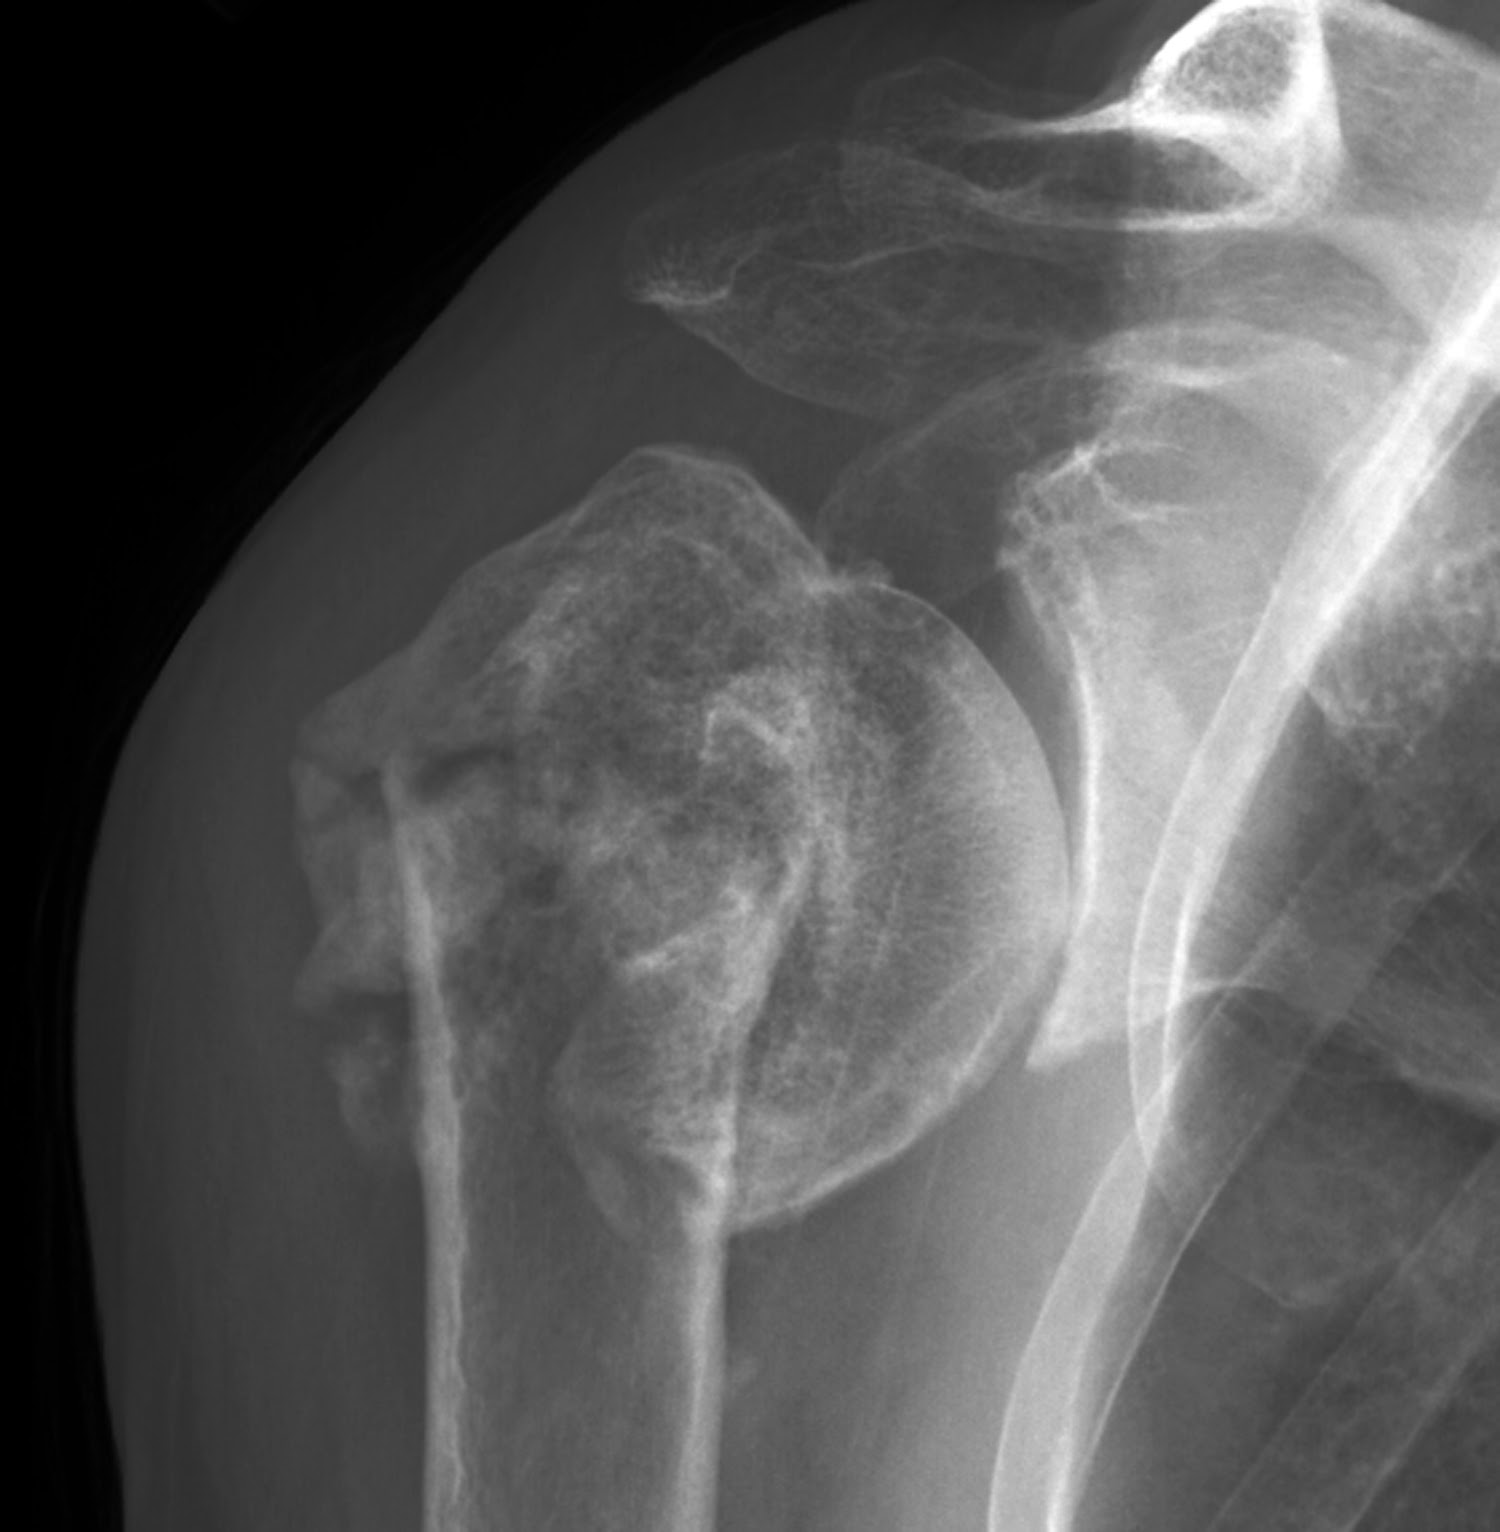

Anterior shoulder dislocation Image Arthritis Dislocated Shoulder a dislocated shoulder is painful and results in temporary loss of mobility and function of the affected arm. in the shoulder, arthritis causes pain and stiffness that can make it difficult to lift your arm, brush your hair, reach up to a high. Pain — you may experience muscle spasms from the. A person with a dislocated shoulder.. Arthritis Dislocated Shoulder.